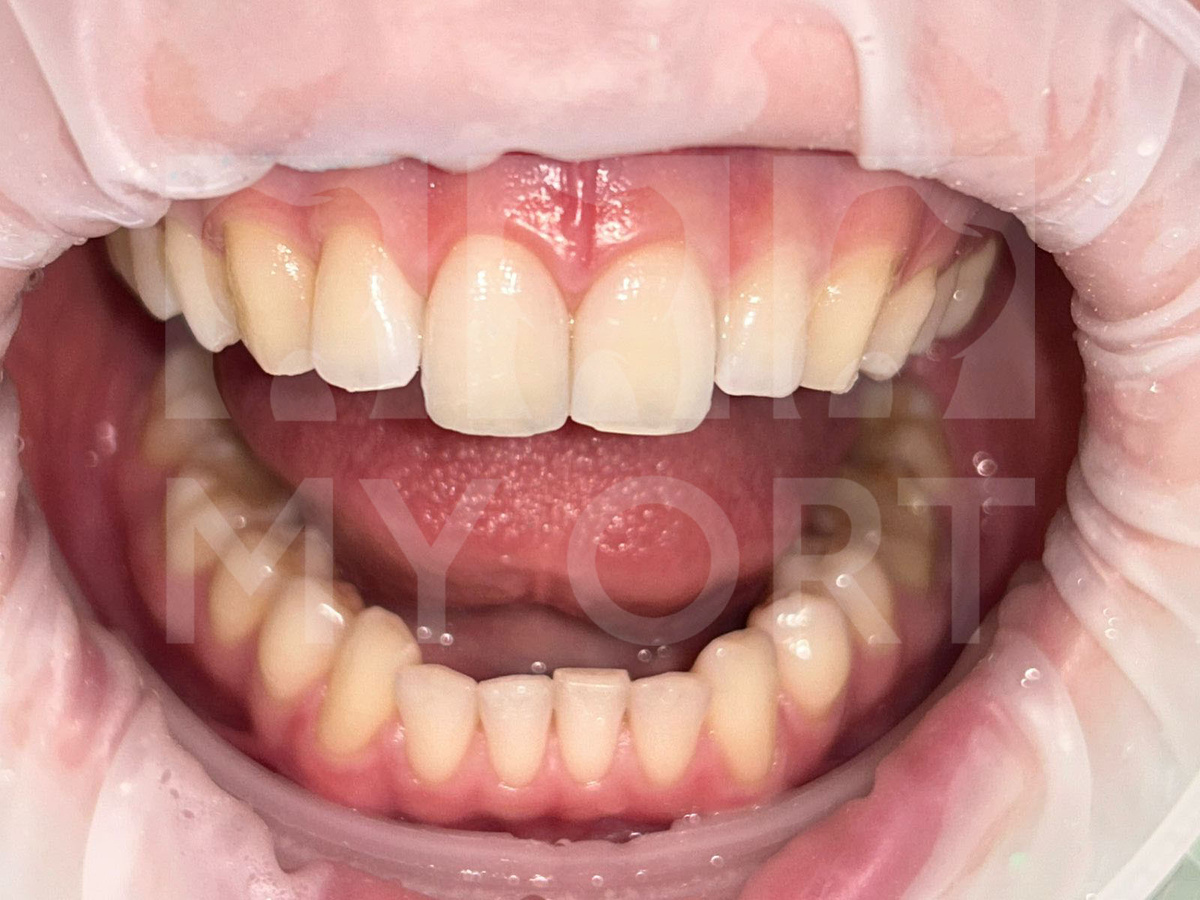

Посмотрите, что у нас получилось! После реставрации зуб остался живым, стабильным, без признаков воспаления. Мы полностью восстановили анатомическую форму и эстетические свойства зуба. Цвет и текстура не отличаются от естественных зубов, функция сохранена.

Пациент остался очень доволен результатом и отметил, что не ощущает никакого дискомфорта. Он может вести привычный образ жизни и не бояться повторных сколов при нормальной нагрузке.